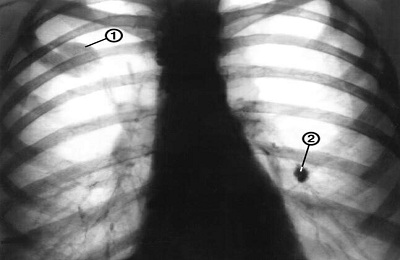

Важно! При центральном раке наблюдается рост опухоли внутрь просвета. При прямой проекции это может быть скрыто тенью сердца.

Поэтому для своевременного выявления патологии специалисты чаще всего проводят снимок сразу в двух проекциях. Определить наличие ателектаза позволяет именно боковая проекция рентгена.

Метастазы в легких на рентгене могут быть определены и в прямой, и в боковой проекциях. Рентгеновский снимок способен показать специфические и неспецифические виды очагов с метастазами. Для некоторых опухолей характерен вид единичных очагов, характеризующихся средней интенсивностью. Метастазы имеют вид дорожек, а их контуры подрытые.

Метастатические поражения присутствуют у каждого третьего пациента, у которого диагностирован рак.

По результатам исследований рентгенолог делает заключение, в котором должно быть подробное описание контуров новообразования, его характер, форма и размеры. Также должны быть тщательно изучены окружающие опухоль мягкие ткани. Правильное лечение пациента во многом зависит от расшифровки рентгенограммы.